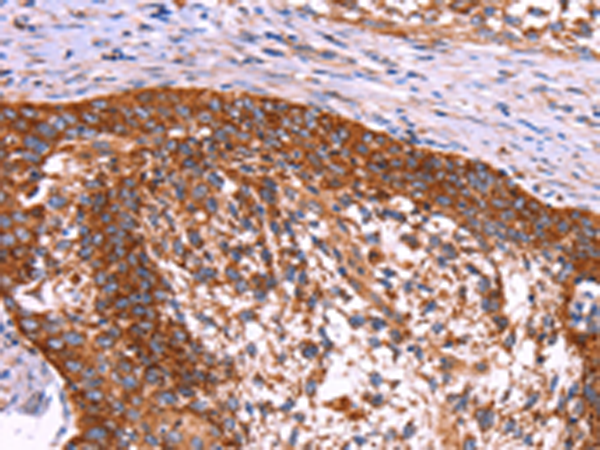

分类: 科研抗体货号: P10621别名: POR1应用: IHC反应种属: Human, Mouse, Rat